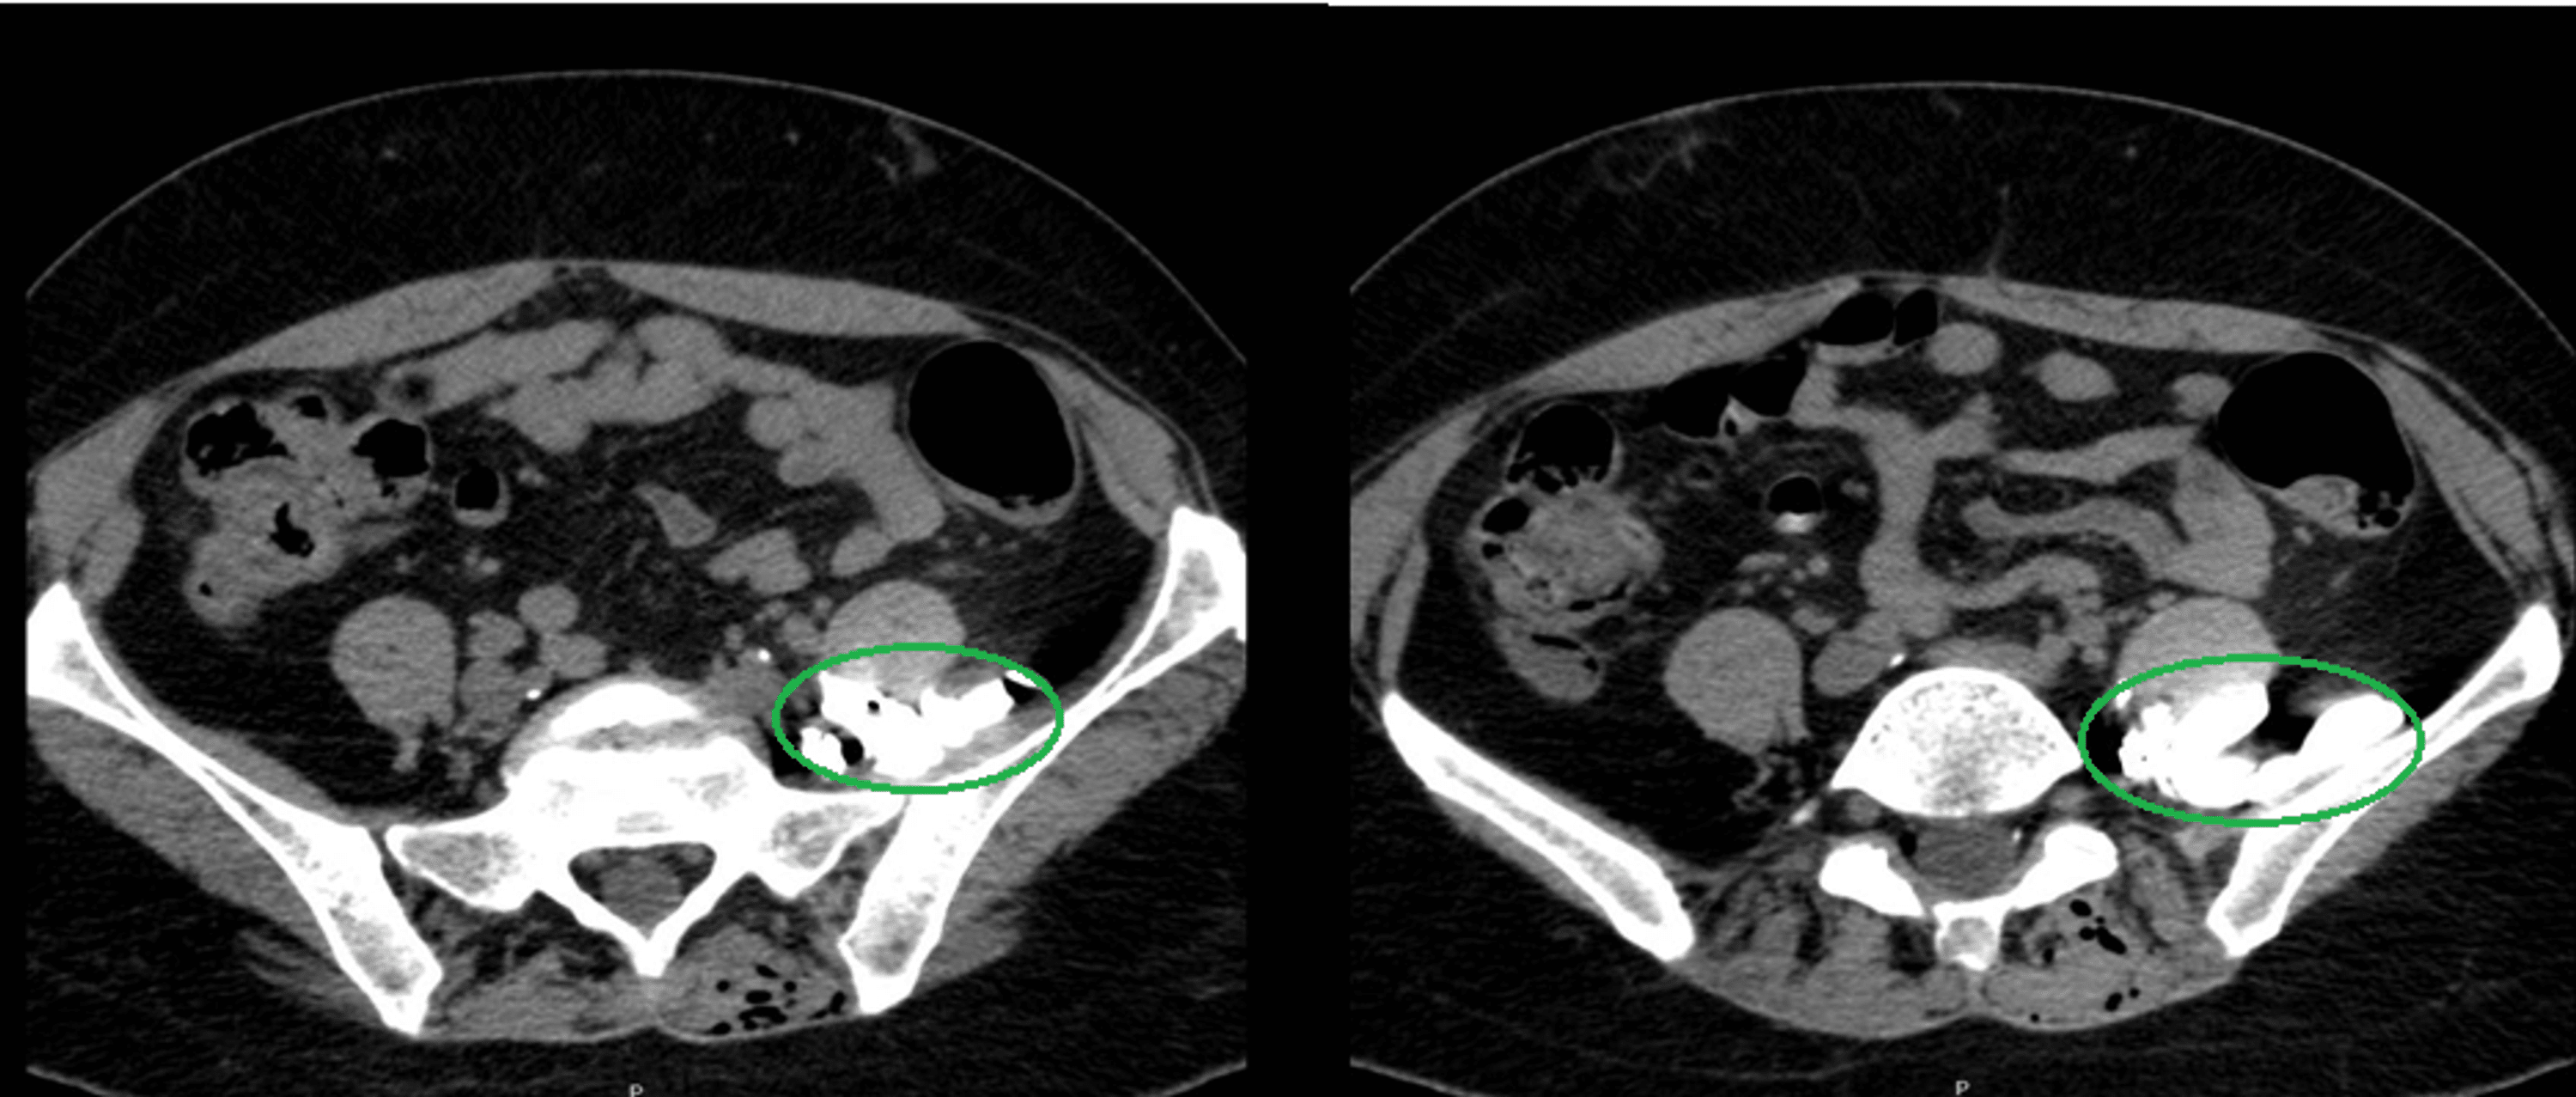

Cureus Epidural Catheter Migration A Case Report of a CT Scan Epidural Catheter Migration Into Subarachnoid Space We present two cases of the insufficient epidural block due to catheter migration, confirmed by a ct scan with. Migration of an epidural catheter into the subarachnoid space can have catastrophic consequences. Although almost all migrations of epidural catheters have been reported to occur at insertion of the catheter, we experienced a case of. We report an apparent delayed perforation. Epidural Catheter Migration Into Subarachnoid Space.